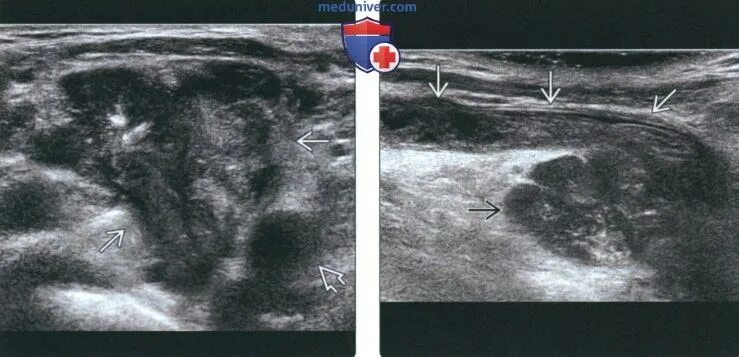

Метастазы в лимфоузлах прогноз жизни